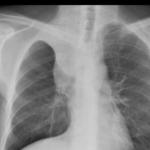

Sarcoid

Album: Sarcoid

Date: 04/20/2004

Size: 63 items

Views: 38281